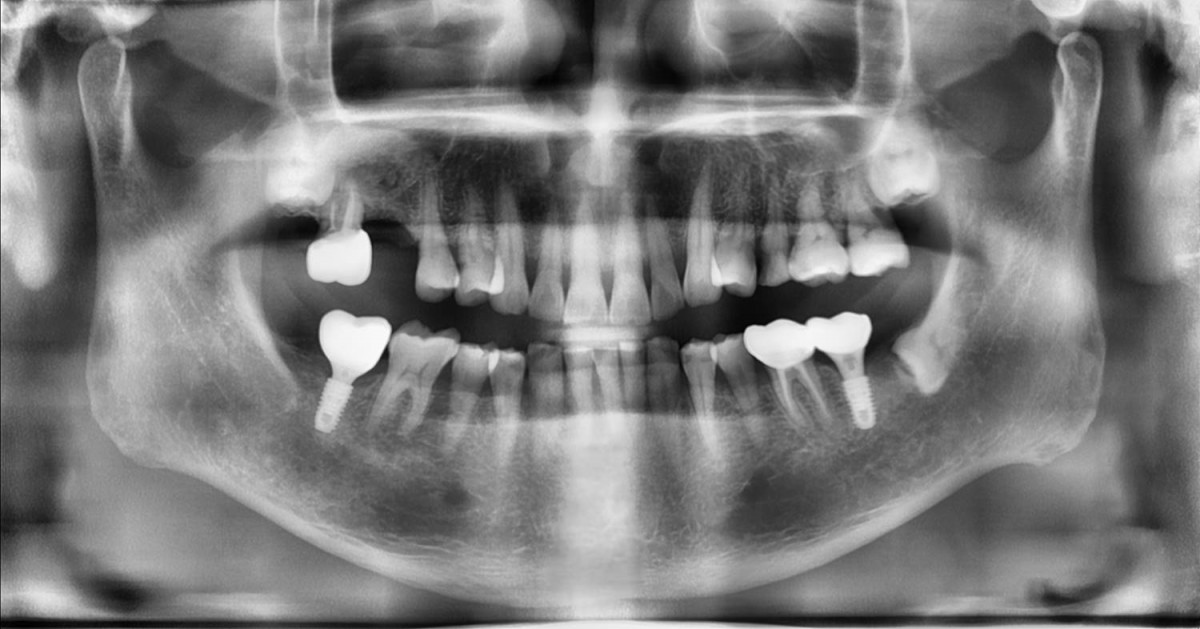

Maxillary Sinus Graft, 2 Implants, Crown Contouring

<GCaks> A 56-year-old male patient had pain-inducing caries, and perio-involved tooth mobility resulted in a tooth fracture at 1st molar. And it was removed months ago. He was a heavy smoker and showed poor oral hygiene.